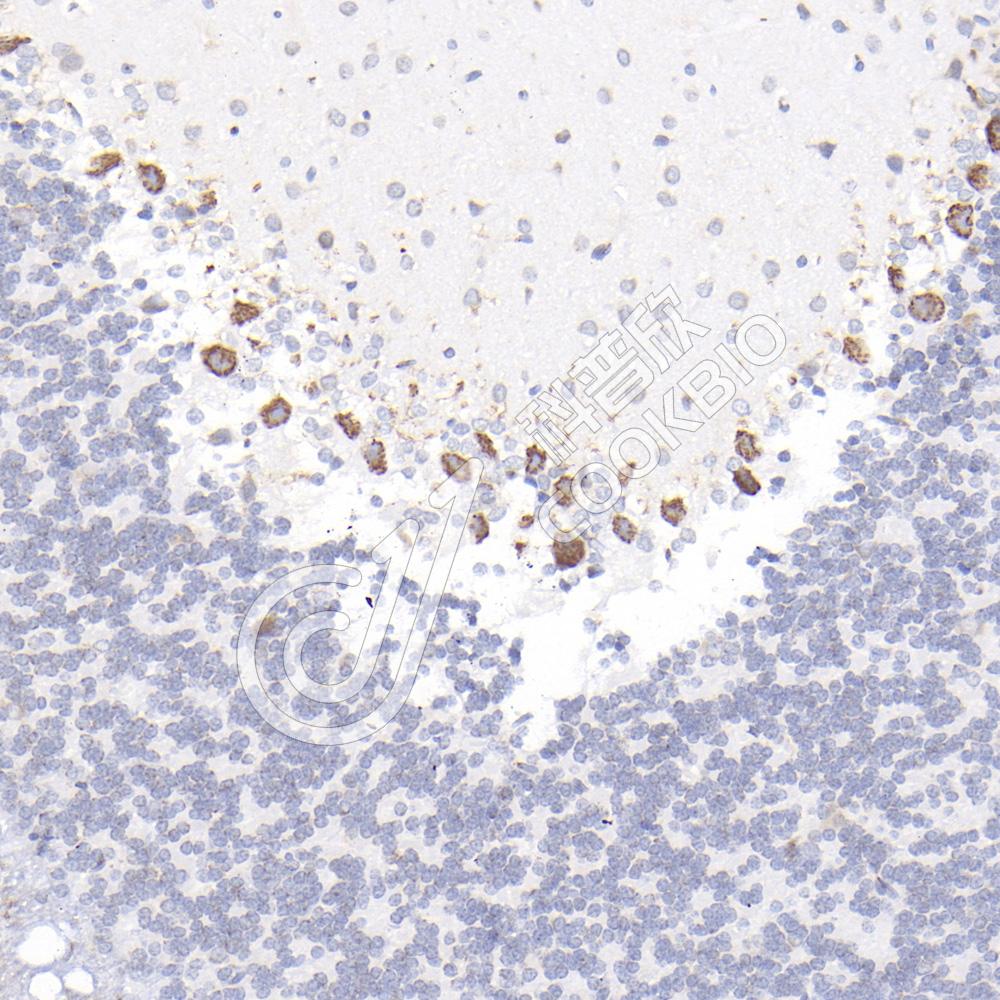

IHC检测CHL1蛋白(货号 K1341226).

样品: 小鼠纹状体, 4%多聚甲醛 (货号KSG1101) 固定12-24小时.

抗原修复: 柠檬酸抗原修复液(干粉, pH 6.0) (KSG1201), 98℃, 20分钟.

—抗: 1: 300稀释, 4℃ 孵育过夜.

二抗: S-vision免疫组化多聚二抗(山羊抗兔),即用型 (货号KB3906), 室温孵育20分钟.

样品: 大鼠小脑, 4%多聚甲醛 (货号KSG1101) 固定12-24小时.